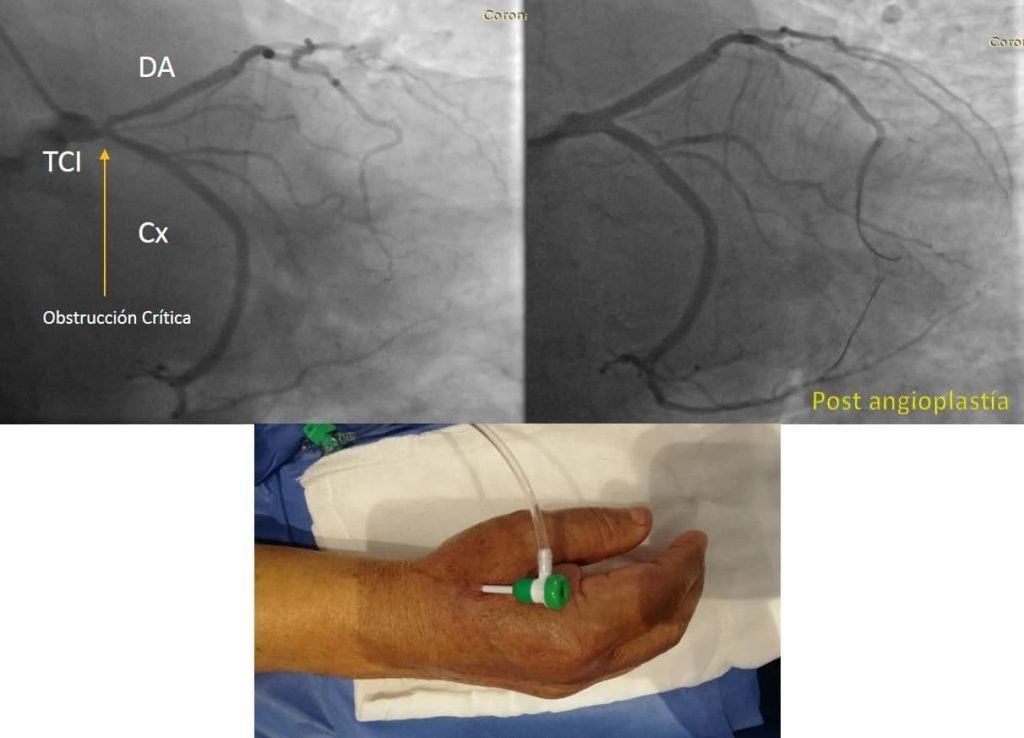

CASO CLINICO DE ANGIOPLASTÍA AL TRONCO CORONARIO IZQUIERDO (ARTERIA PRINCIPAL DEL CORAZÓN)

Hombre de 68 años con diabetes mellitus e hipertensión, presentaba angina de pecho, se realiza cateterismo cardiaco + angioplastía exitosa con 2 stents a la arteria principal del corazón, todo mediante una sola punción en la arteria radial.